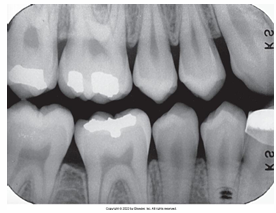

What is the problem with this UNDERDEVELOPED FILM X-ray?

Appears light, Inadequate development time, Developer solution too cool, Inaccurate timer or thermometer, Depleted or contaminated developer solution

How would you resolve this UNDERDEVELOPED FILM X-ray?

Check development time, Check developer temperature, Replace faulty time or thermometer, Replenish developer with fresh solutions as needed